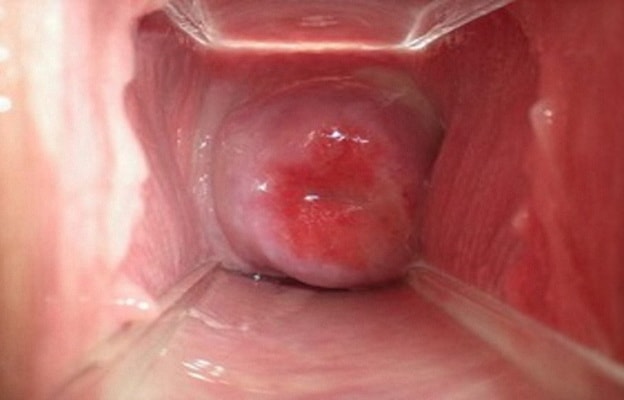

2. Эрозия шейки матки (эндоцервикоз).

Является одним из наиболее часто встречаемых заболеваний среди женского населения. Практически 40% всех женщин сталкиваются с эрозией, из них 55% составляют женщины в возрасте до 25 лет. Эрозия шейки матки представляет собой дефект слизистой оболочки наружной части шейки матки, пусковым моментом которой чаще всего является инфекционный воспалительный процесс.

Все это приводит к тому, что изменяется структура слизистой оболочки шейки матки, многослойный эпителий ее в месте повреждения исчезает, а поверхность слизистой оголяется. В итоге образуется истинная эрозия шейки матки.

Обычно через 1-3 недели истинная эрозия заживает или переходит в псевдоэрозию шейки матки, когда многослойный эпителий эрозии замещается цилиндрическим эпителием из цервикального канала шейки матки.

Обычно эрозия протекает бессимптомно и ее обнаруживают при гинекологическом осмотре, очень редко может проявляться кровянистыми выделениями после полового акта. При отсутствии лечения эрозия может перейти в онкологический процесс.

Эрозия шейки матки

Под эрозией шейки матки понимается нарушение слизистой оболочки маточной шейки. Это одна из самых распространенных женских болезней.

Явление доброкачественное, но его необходимо постоянно наблюдать.

Причинами часто становятся воспаления женских половых органов, раннее начало половой жизни, травмы, ослабление иммунитета, гормональные сбои. Могут способствовать эрозии эндокринные патологии.

Нередко заболевание обнаруживается только при осмотре. Иногда возможны небольшие кровотечения, особенно после интимного акта. Может проявляться болезненность. Если присоединяется инфекция, возможен зуд, выделения с запахом.

Эрозия шейки матки (имеются и другие названия: эктопия, псевдоэрозия), представляет собой отклонение в строении слизистой части влагалища или нарушение ее целостности. Образоваться эрозия может у любой женщины, независимо от возраста. Заметив такое заболевание нужно незамедлительно переходить к его лечению, после обязательного, полноценного и тщательного обследования.

Если вовремя не начать лечить такую болезнь, в дальнейшем она может повлечь за собой образование раковых клеток. Особо опасно это для тех женщин, у которых присутствует вирус папилломы, так как он приводит к повышенному риску образования опухоли. А также это опасно и для тех, у кого присутствует вирус герпеса, при нем вероятность образования злокачественных опухолей гораздо выше.

Во время осмотра эрозия отражена в зеркале, как небольшой участок красного цвета, окружающий наружный зев. Размер ее колеблется от двух миллиметров до двух сантиметров. Держится эрозия в организме несколько месяцев и даже лет.